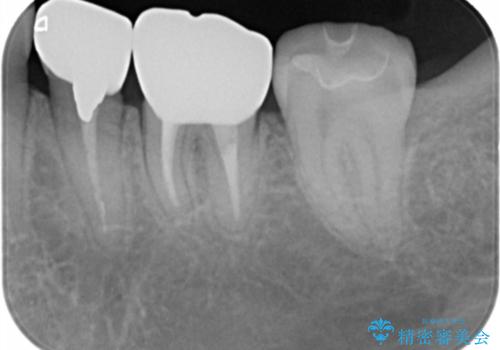

- 左下の銀歯二本のやりかえを希望。(左下5および左下6)

高さがないため、歯肉と歯槽骨の手術(歯周外科手術)APFを行ってから、最終的な被せ物にしました。

- 44万円 左下5:仮歯、セラミッククラウン 左下6:精密根管治療(再治療)ファイバーコア、仮歯、セラミッククラウン費用は治療当時の料金となります